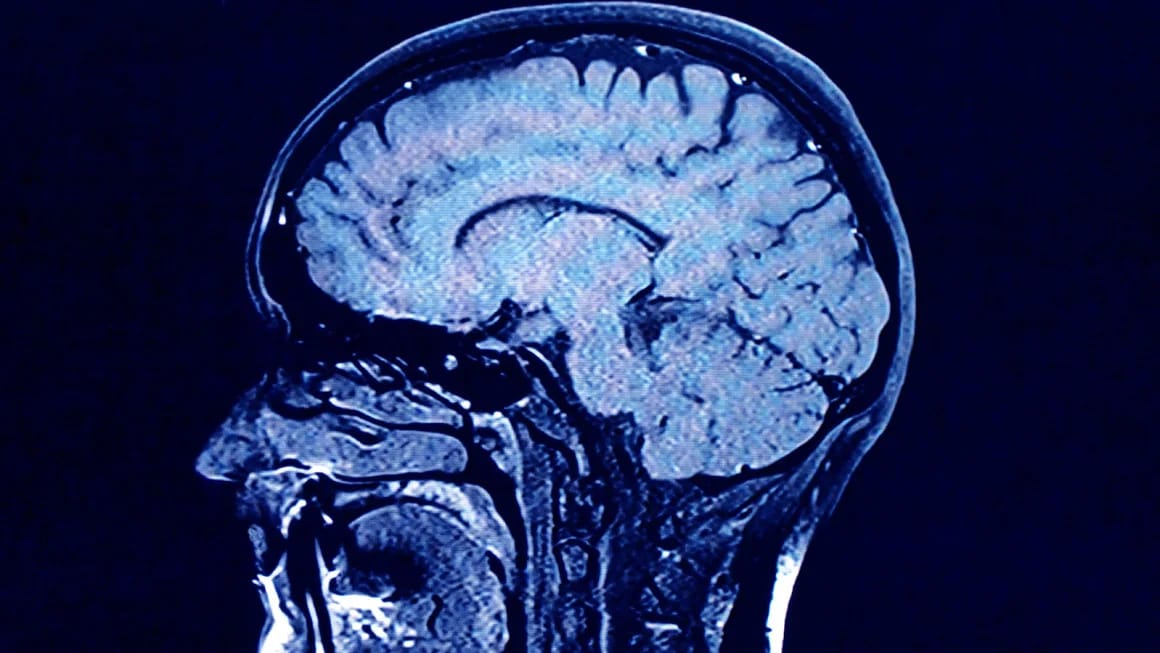

هەڵبژاردنی شێوازی ژیان لە تەمەنێکی پێگەیشتوو بەشدارە لە باشتربوونی تەندروستی میشک.، سەرچاوە: CNN

هەندێک هۆکاری شێوازی ژیان یارمەتیدەر دەبن بۆ کارکردنی مێشک بەشێوەیەکی تەندروستتر لەگەڵ تەمەن، وەک وەرزشکردن، دوورکەوتنەوە لە جگەرەکێشان و خواردنەوە کهولییەکان، فێربوونی زمانی دووەم یان ژەنینی ئامێرێکی میوزیک.

توێژینەوەی فەرمی: توێژەرانی زانکۆی Edinburgh بۆیان دەرکەوتووە پیربوونی مێشک لە نێوان مرۆڤەکاندا زۆر جیاوازە، باس لەوە دەکەن نزیکەی نیوەی جیاوازییەکانی پیربوونی مێشک ڕەنگە بگەڕێتەوە بۆ تواناکانی منداڵی، لەکاتێکدا هەڵبژاردنی شێوازی ژیان لە تەمەنێکی پێگەیشتوو بەشدارە لە باشتربوونی تەندروستی میشک.

ئەنجامی توێژینەوە: هەندێک مێشک وەک مێشکی گەنجێکی پێگەیشتوو دەرکەوتوون، لەکاتێکدا هەندێکی تریان پیر دەرکەوتوون، ئەمەش بەهۆی خووە خراپەکانی وەکو جگەرەکێشان و خواردنی ناتەندروست و وەرزشنەکردن.

ئاماژە بۆ ئەوەش کراوە لەکاتێکدا هەندێک پیربوونی مێشک حەتمییە، بەڵام هۆکارەکانی شێوازی ژیان دەتوانن کاریگەرییەکی بەرچاویان هەبێت لەسەر ئەوەی کە مێشکمان چەندە باش پیر دەبێت.

لێدوانی فەرمی: شارەزایان دەڵین خووی بچووک و تەندروست بە تێپەڕبوونی کات تەندروستی مێشک دەپارێزن. د.ڕیچارد ئیزاکسۆن، بەڕێوەبەری پەیمانگای نەخۆشیی میشک و دەمار لە ویلایەتی فلۆریدای ئەمریکا، جەخت لەسەر گرنگیی وەرزشی بەردەوام و خۆراکی تەندروست بۆ دڵ و خەوێکی باش و بەڕێوەبردنی پەستانی خوێن و کۆلیسترۆڵ و فشاری دەروونی دەکاتەوە، بۆ کەمکردنەوەی مەترسییەکانی نەخۆشی بیرچوونەوە و دابەزینی توانای مێشک.